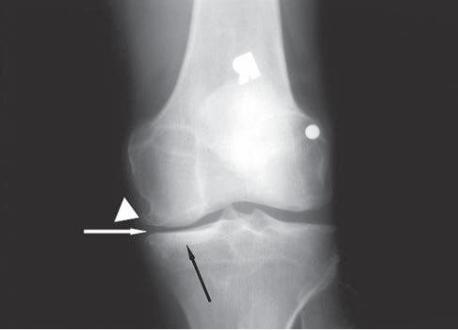

Рентгенологическая картина ОА по Kellgren

0 – Изменения отсутствуют

I – Сомнительные рентгенологические признаки

II – Минимальные изменения (небольшое сужение суставной щели, единичные остеофиты)

III – Умеренные проявления (умеренное сужение суставной щели, множественные остеофиты)

IV – Выраженные изменения (суставная щель почти не прослеживается, выявляются грубые остеофиты